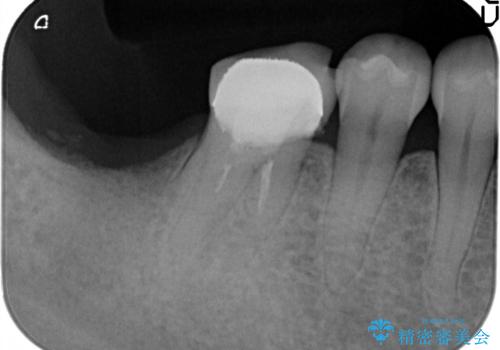

- 失った右下最後方臼歯の咬合機能の回復を求めてインプラント治療を希望され来院されました。

インプラントを埋入するのに十分な骨の量がCT検査により確認されたので、インプラントによる治療を計画します。